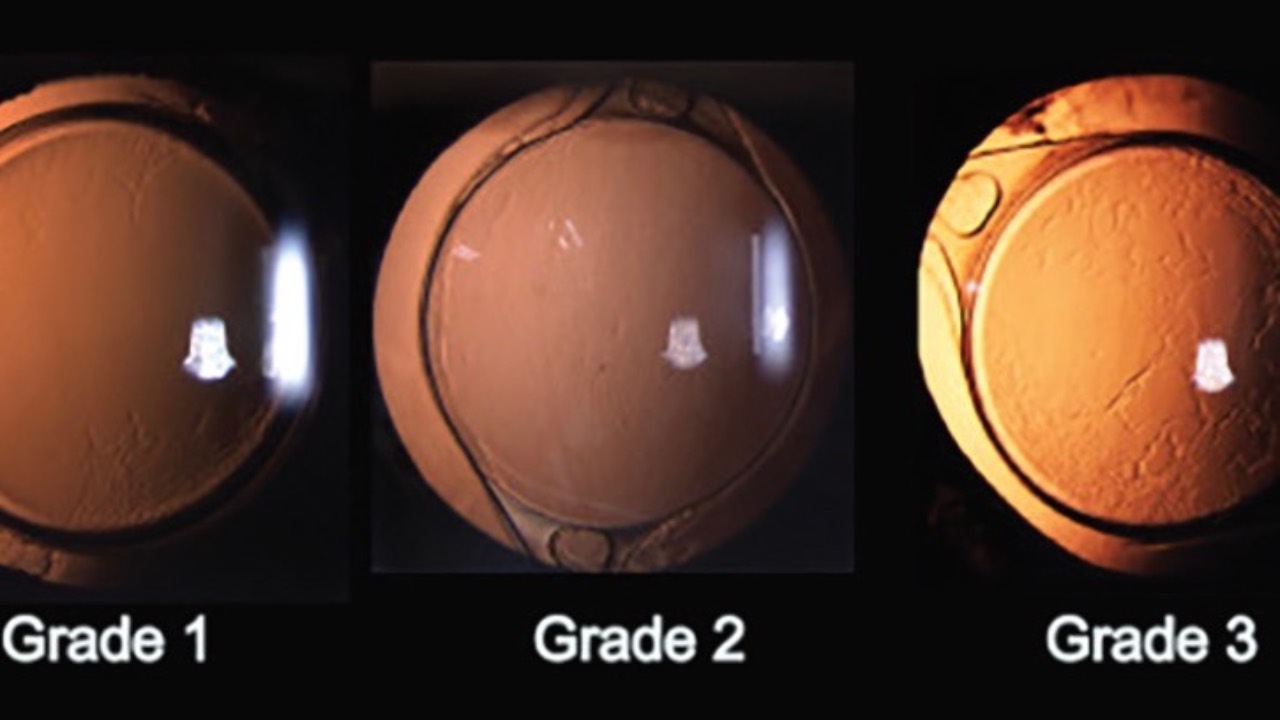

Yag Capsulotomy Timing

Do you know why & when it's best to pull the trigger?...

Determining the optimal timing for a YAG capsulotomy following cataract surgery requires understanding several factors to ensure safety and quality outcomes.

Considerations include complete resolution of post-operative inflammation, positi...